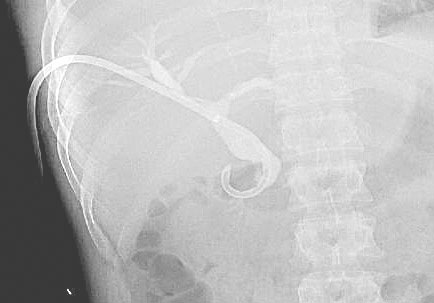

2)T管造影:肝内外胆管未见明显充盈缺损,胆总管下段通畅(图6)。

图6 T管造影